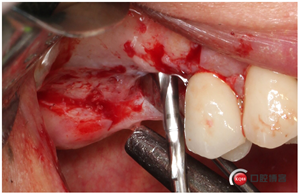

這個(gè)東西叫窗口修整鉆,頭兒是圓的且很光滑,四周是有切割功能的,用圓頭頂開(kāi)上頜竇膜800-1200轉(zhuǎn)速修整窗口邊緣。

我有好的工具我任性,看看我在遠(yuǎn)中用幾秒鐘的時(shí)間再開(kāi)一個(gè)窗口。

用大直徑的修整鉆修理邊緣,形成一個(gè)規(guī)則的橢圓形窗口。

當(dāng)然了,雖然開(kāi)始有水壓剝離,但不見(jiàn)得我們需要的位置都能撥開(kāi),還需進(jìn)一步剝離一下。然后牙槽嵴頂備洞。